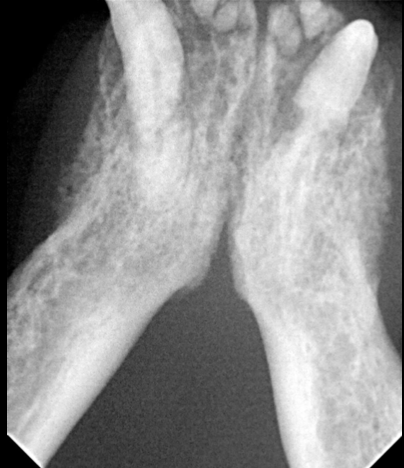

Quelles sont les lx?

Perte osseuse sur 404 et poche infra-osseuse sur 304